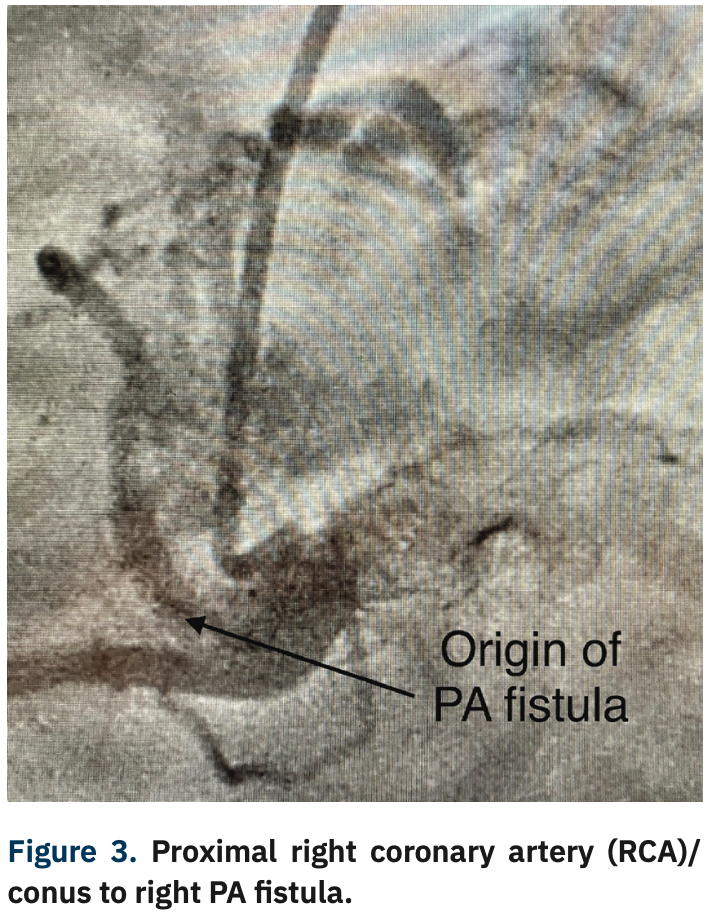

She underwent a coronary angiogram via right radial artery approach utilizing the hyper adducted right radial artery (HARRA) method3 (Figure 1), with angiography showing a normal left main and left circumflex coronary artery. There was a 50% stenosis in the mid LAD and mid right coronary arteries (Figure 2). Angiography also revealed a fistula connection between the proximal LAD and the left pulmonary artery, as well as the conus branch of the RCA and right pulmonary artery (Figures 3-5).